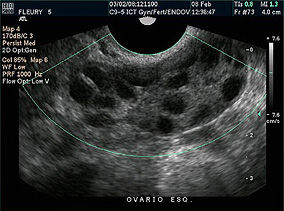

Presença de múltiplos pequenos cistos nos ovários ao ultrassom, chamados tecnicamente de folículos antrais.

O exame de ultrassom ajuda, mas não é suficiente para identificar a síndrome. O achado isolado de aumento dos folículos antrais ao ultrassom não fecha o diagnóstico de síndrome do ovário policístico.

Na Síndrome dos Ovários Policísticos (SOP), os ovários ficam repletos de múltiplos folículos antrais que param de crescer e não chegam ao momento da ovulação (os chamados “microcistos ou cistos”). Em portadoras da síndrome, esses cistos permanecem e modificam a estrutura dos ovários, tornando-os maiores que o normal.